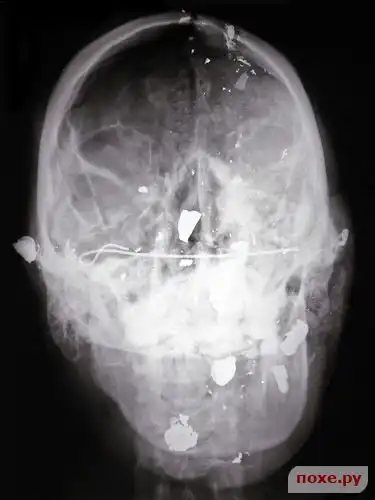

Выстрел из дробовика в голову.

Многочисленные выстрелы в голову.